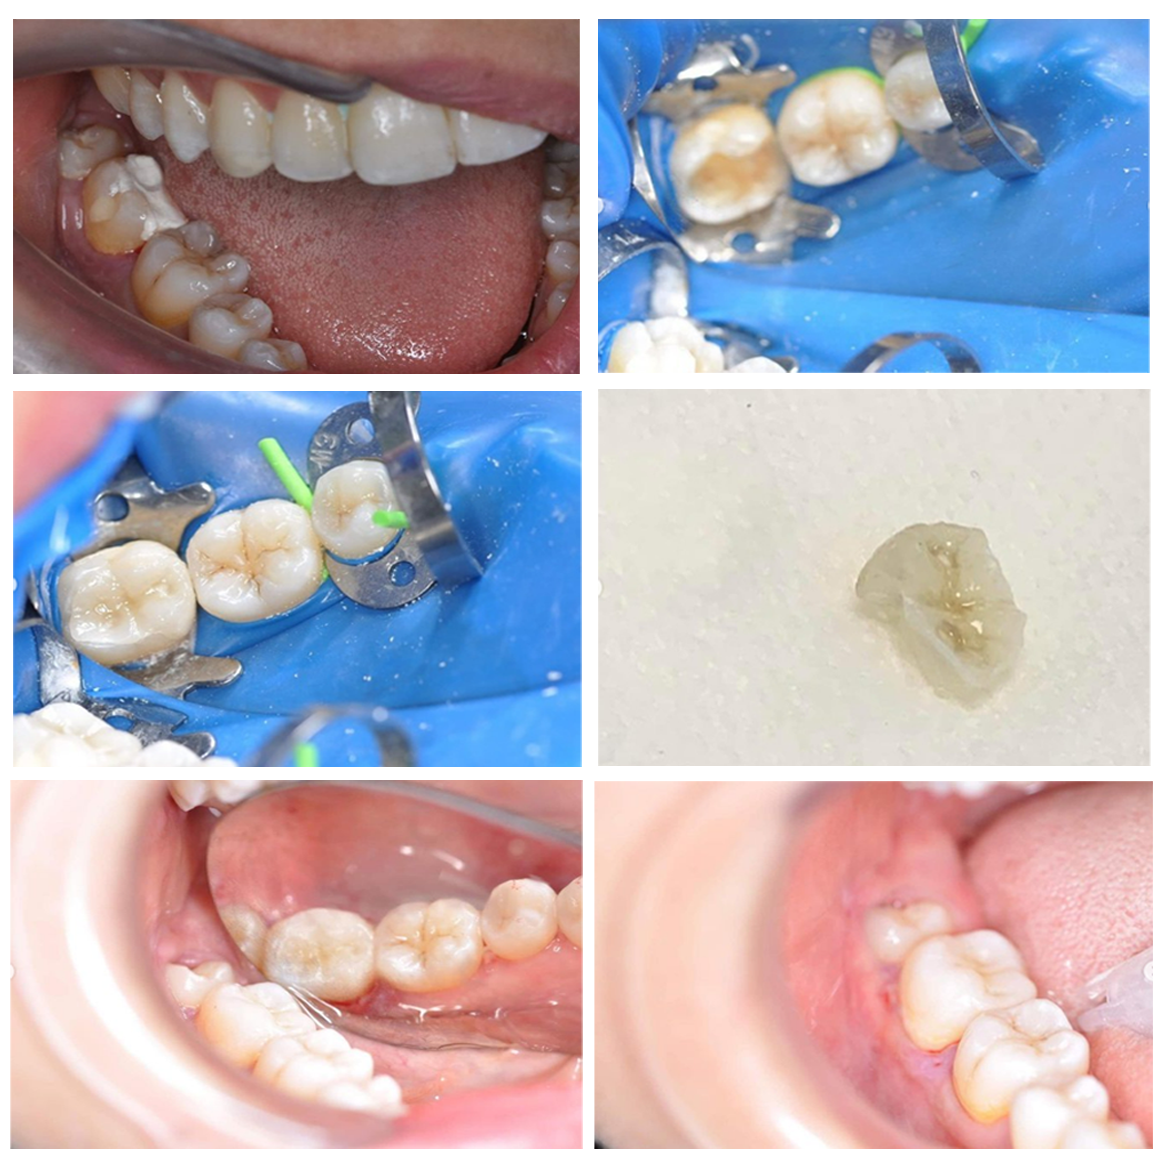

Inlay en emax

Inlay en emax pour une meilleure restauration de la surface de contact interdentaire et une meilleure santé parodontale

Correction d'un sourire gingival

Correction d'un sourire gingival par un repositionnement labial